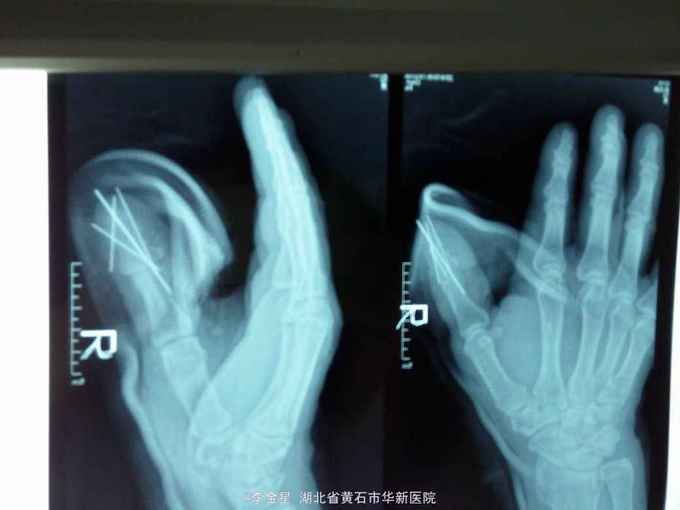

查体:生命体征平稳,左拇指末节甲根部以远指体见多处皮肤挫裂伤口,甲盖剥脱,甲床破损,各创缘不齐,伤口出血活跃,污染挫伤重。见多处拍片示:左拇指末节粉碎性骨折。

左拇指压砸伤:左拇指末节粉碎性骨折伴甲床损伤